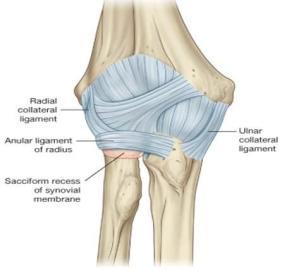

Describe the anatomical position of the collateral ligaments of the elbow joint